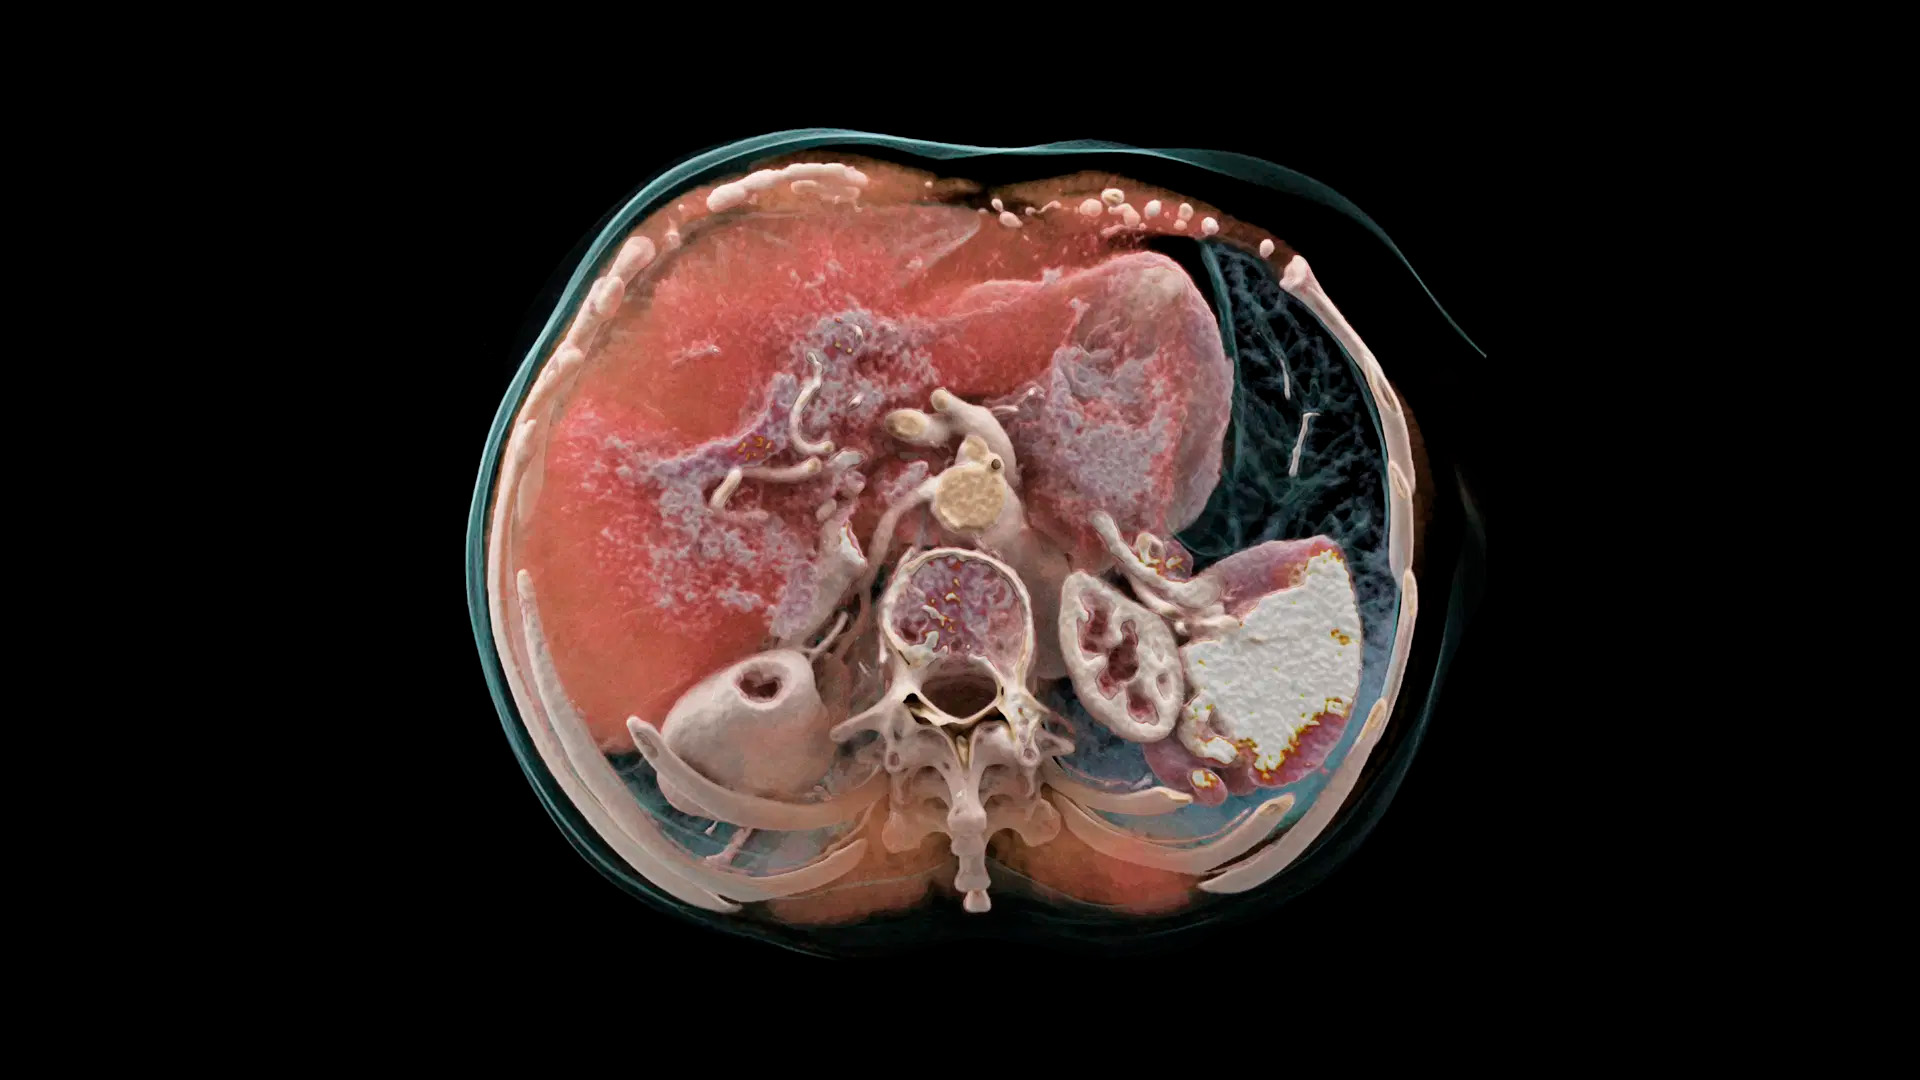

Квантовая спектральная визуализация

Получайте спектральные карты при каждом сканировании, независимо от скорости сканирования, поля обзора или пространственного разрешения. Это обеспечивает точную функциональную оценку без каких-либо компромиссов.

Квантовая итерационная реконструкция

Обеспечьте оптимальное качество изображения и снижение уровня шума с помощью итеративной реконструкции спектральных данных на основе моделей с полной синхронизацией между потоками данных и с высокой и низкой энергией.